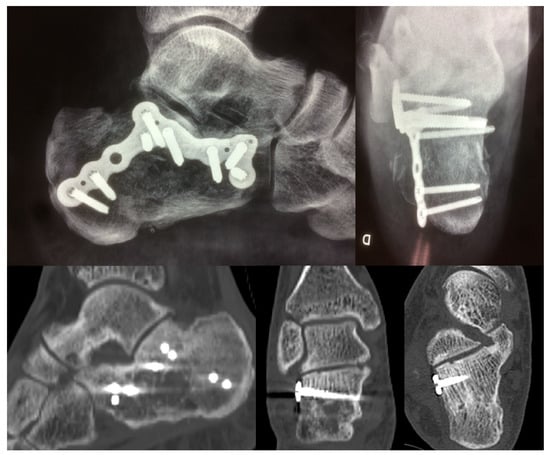

2.2. Surgical Procedure

| Patient Position | Lateral Decubitus |

| Intra-operatory aids | C-arm fluoroscopy |

| Anatomical markers | Tip of the lateral malleolus Base of the 4th metatarsal bone |

| Fragments exposure | Release of the inferior peroneal retinaculum Release of the CFL and subtalar ligaments SJ exposure |

| Steps for fragments reduction | Reduction of the PT fragment to the sustentacular constant fragment Reduction of articular fragments from posterior to anterior |

| Osteosynthesis | Temporary fixation with K-wires IF with plate and screws |

| Wound closure |